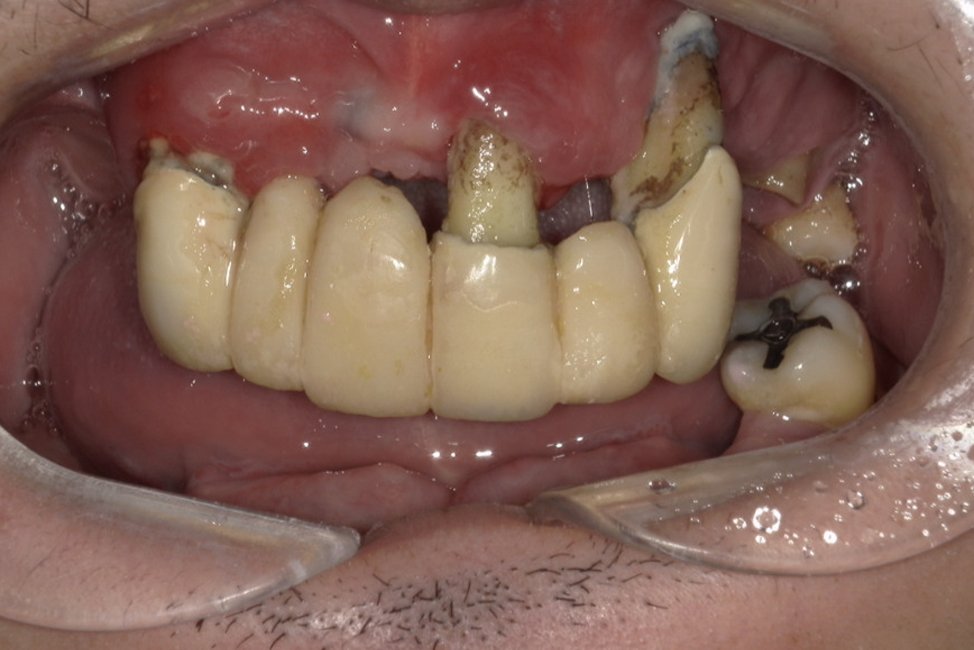

| 主訴 | 歯がグラグラして噛めない |

|---|---|

| 治療内容 | 上顎、下顎に対するインプラント治療 |

| 治療期間 | 1日 |

| 治療費 | 409万2千円 |

| 治療 リスク | 最終的な歯が入るまでは仮歯になります。 |